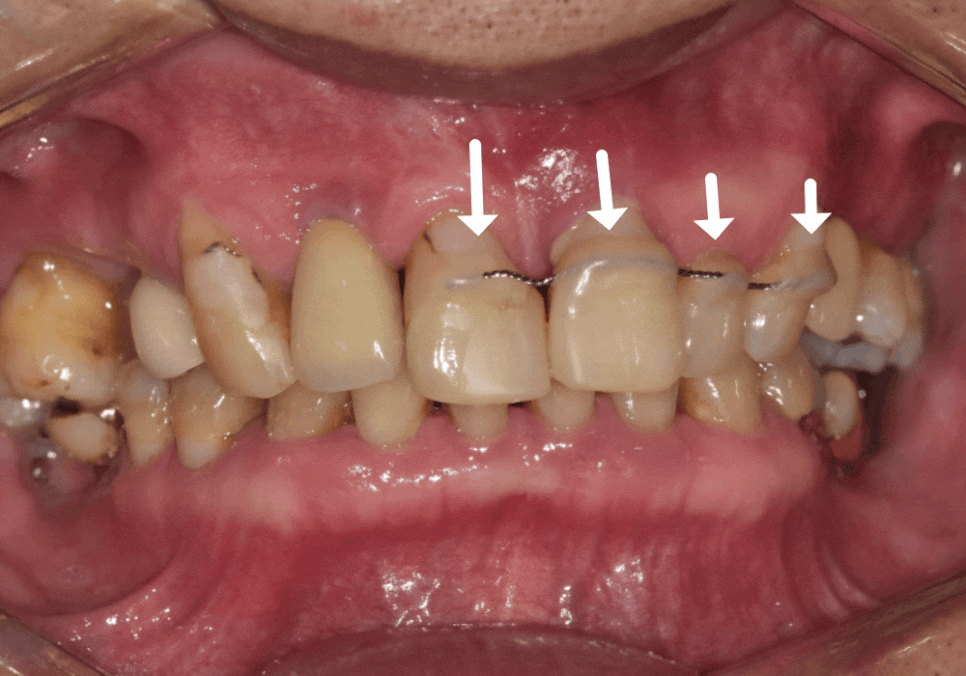

하지만, 방사선 사진과 입안을 살펴보니,

오른쪽 작은 어금니(#15) : 발치로 인해 치아 상실된 상태, 뼈가 다량 녹은 상태

앞니 3개 (#11,21,22) : 복합 치주염으로 뼈가 녹아 잇몸 상태가 좋지 않고 흔들림이 심함

250106 기존 뼈보다 녹은 뼈 상태

만약, 보장을 위해 1년 더 기다리게 된다면

앞니 쪽은 더 흔들리고

잇몸이 더 내려갈 가능성이 컸습니다.

추후 뼈이식과 잇몸 이식까지

병행한다면 보장비용보다

환자분이 내야 할 비용이

더 클 수 있는 상황이었죠.

그래서 치료를 더 미루기 어려웠습니다.